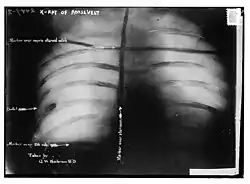

Afterwards, probes and an x-ray showed that the bullet had lodged in Roosevelt's chest muscle, but did not penetrate the pleura. Since doctors concluded that it would be less dangerous to leave it in place than to attempt to remove it, Roosevelt carried the bullet with him for the rest of his life.

Afterwards, probes and an x-ray showed that the bullet had lodged in Roosevelt's chest muscle, but did not penetrate the pleura. Doctors concluded that it would be less dangerous to leave it in place than to attempt to remove it, probably remembering what had happened to Roosevelt's immediate predecessor who died after the bullet's wound got infected, and Roosevelt carried the bullet with him for the rest of his life.[16][17] In later years, when asked about the bullet inside him, Roosevelt would say, "I do not mind it any more than if it were in my waistcoat pocket."[18]